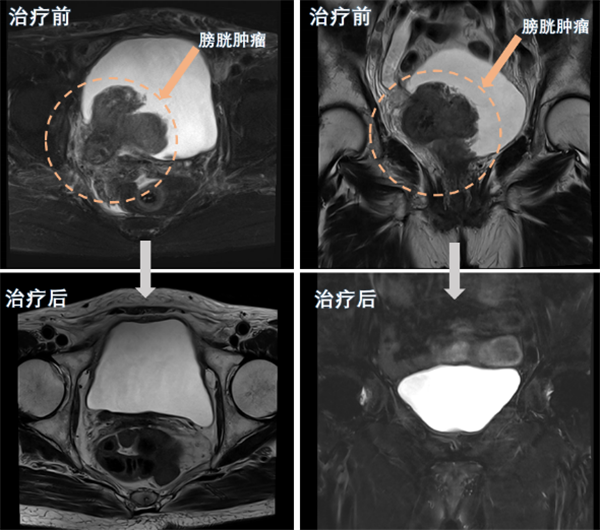

近日,糖心vlog (简称中山一院广西医院)泌尿外科团队为一名80岁高龄的巨大膀胱肿瘤患者实施了经尿道膀胱肿瘤剜除术及术后精准综合治疗,成功保住了该患者的膀胱。经过四个周期的综合治疗后,患者膀胱恢复完好,未见肿瘤复发。该手术的成功,标志着我院泌尿外科在膀胱癌诊治和保膀胱治疗技术方面取得了新突破。半年前,80岁的苏奶奶(化名)因反复无痛性肉眼血尿在当地医院就诊,经...